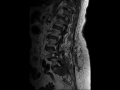

Myxopapillary Ependymoma

There is an enhancing mass centered in the body and left ala of the sacrum. Several enahncing nodules were additionally seen along the cauda equina nerve roots. This was a histopatholigically known myxopapillary ependymoma with recurrence after initial resection. This is a relatively uncommon but described presentation of this type of lesion, which otherwise classically are centered in the region of the conus medullaris, cauda equina and filum terminale.